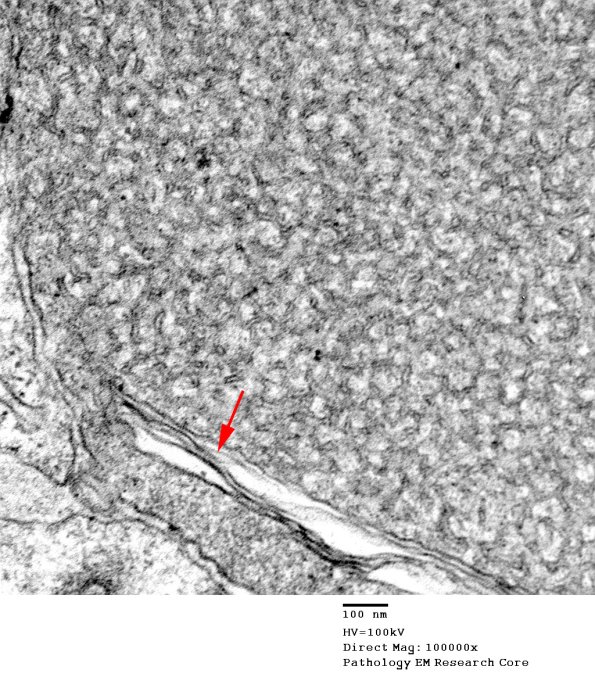

Higher magnification of image #1B1B. (electron micrograph)